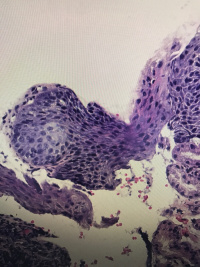

食道粘膜

腹痛,距门齿33cm处食管壁见0.4✖️0.5cm隆起

灰白组织一粒,直径0.1

鳞状上皮乳头状瘤性息肉,局部鳞状上皮轻度异型增生。

鳞状上皮下是幽门腺,胃粘膜异位

鳞上皮乳头上移,副基底层增生